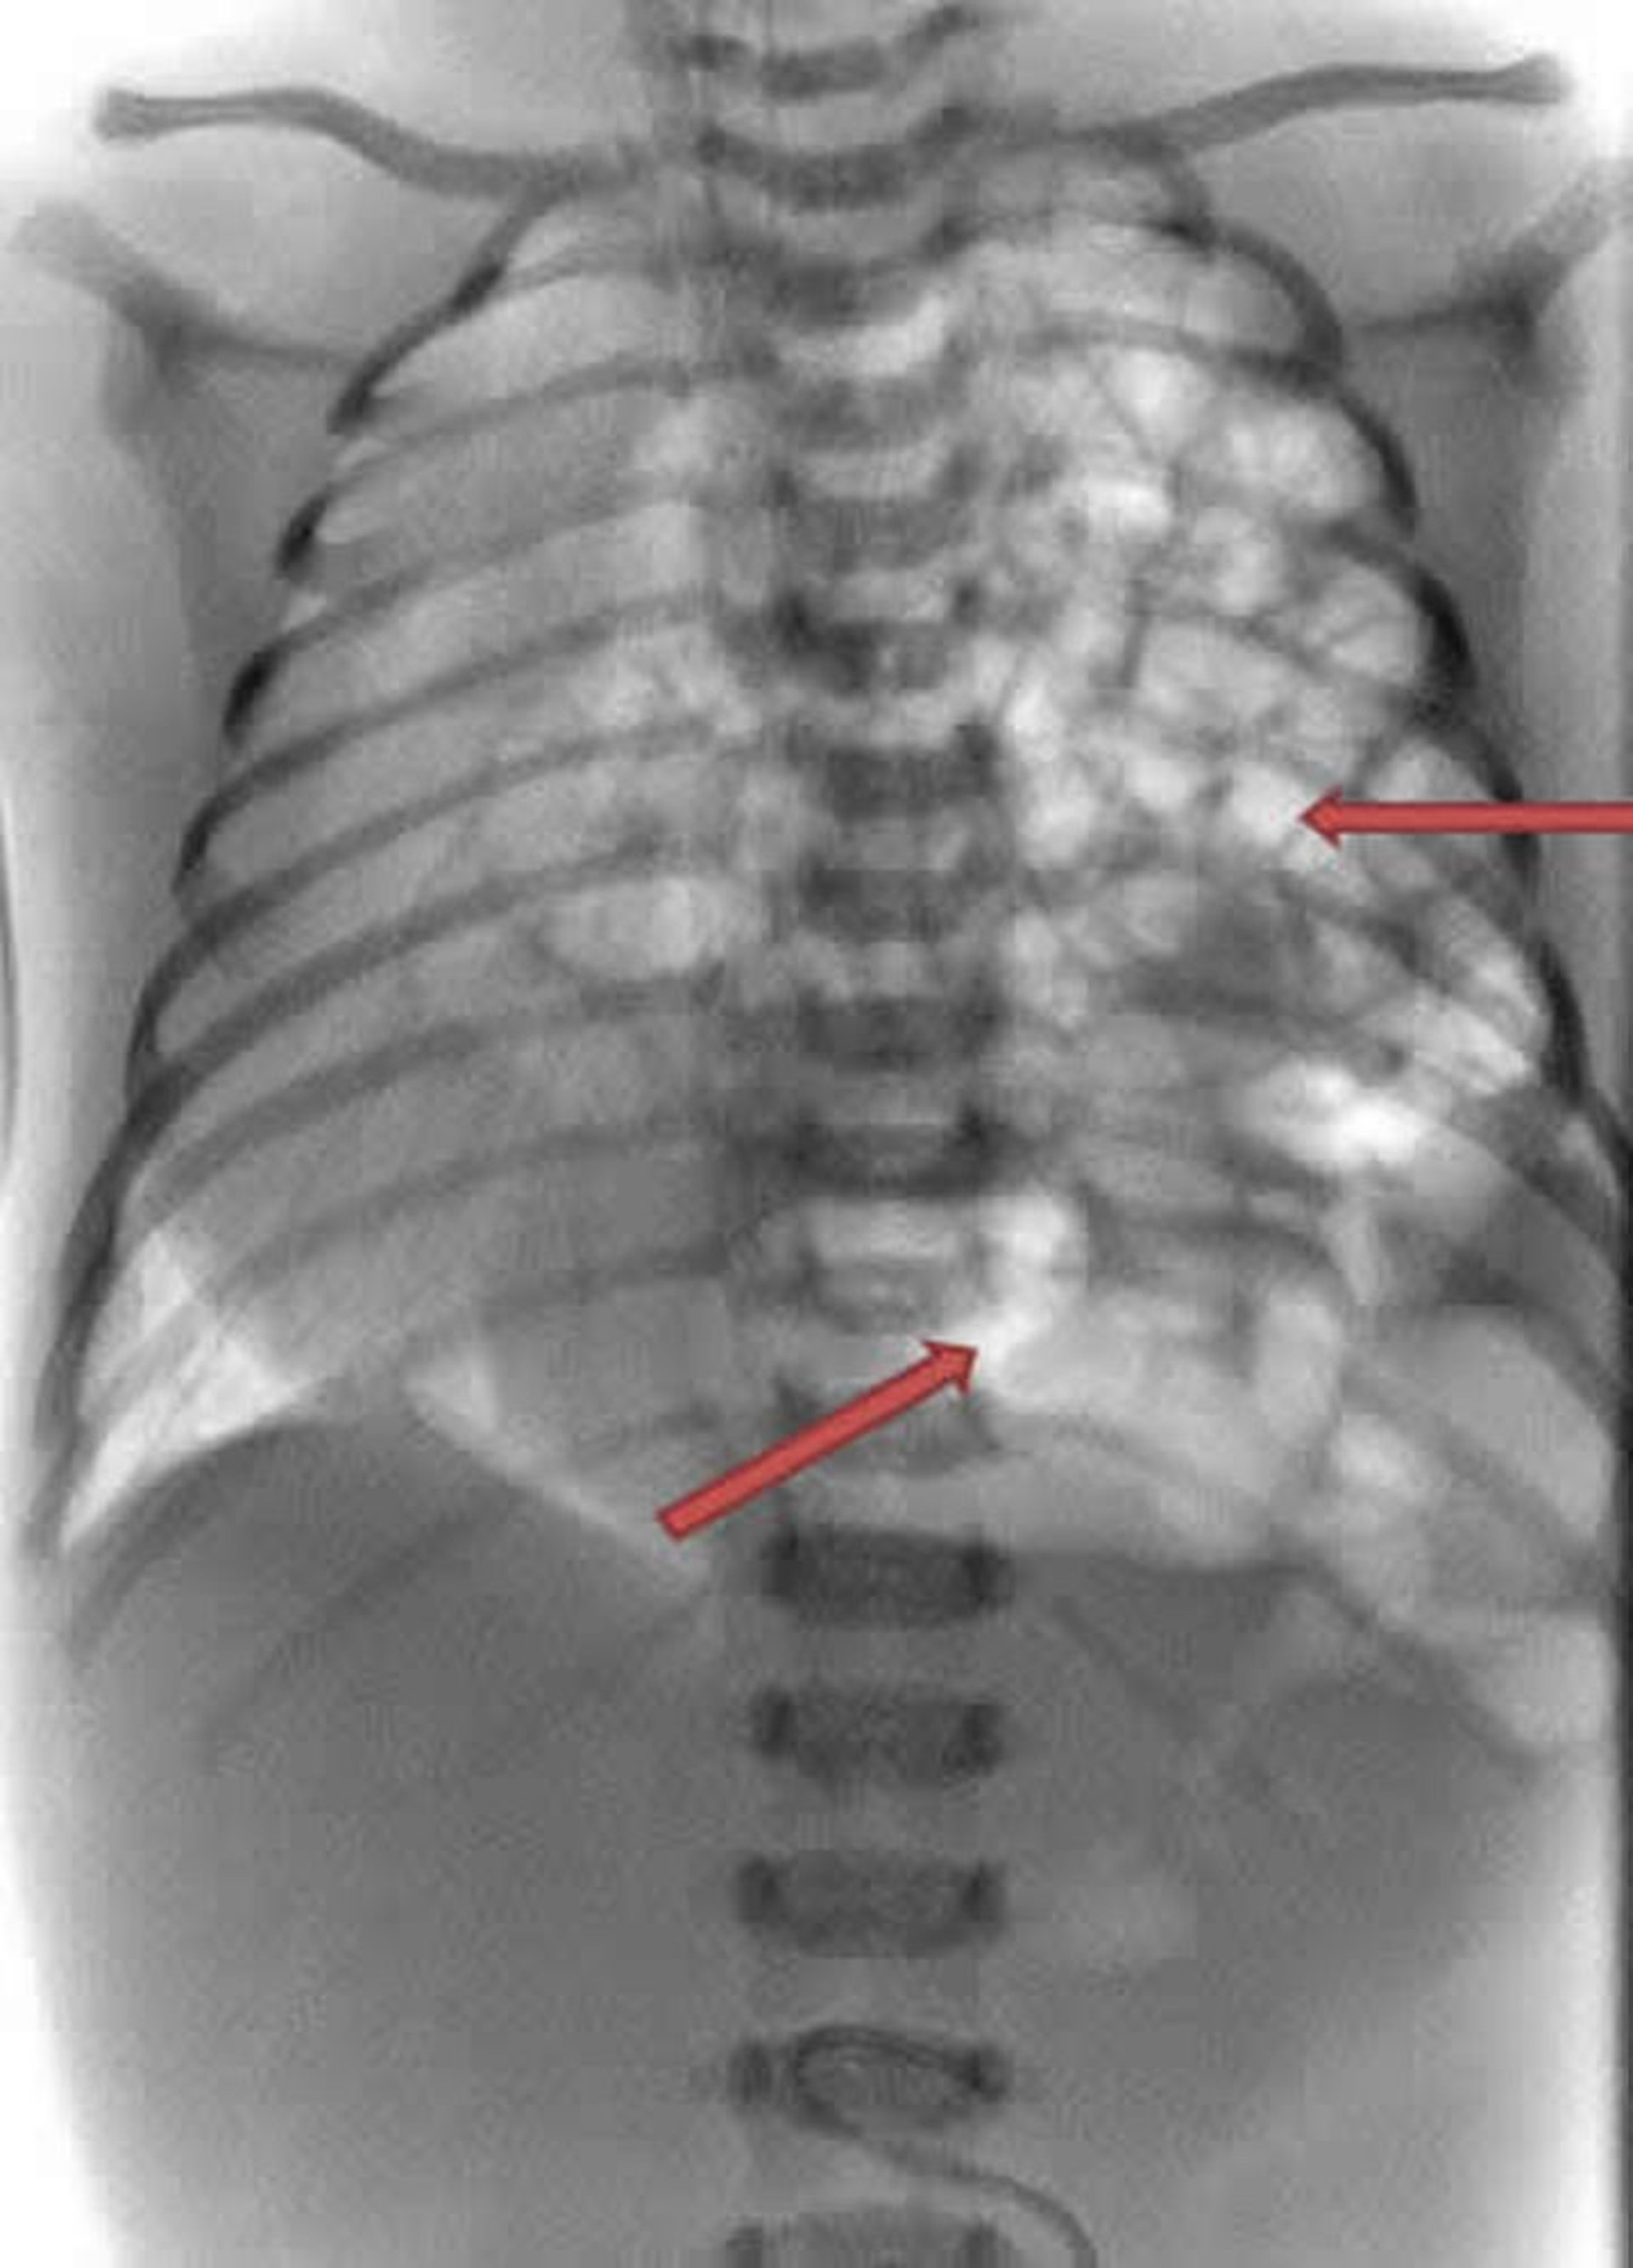

Hernie diaphragmatique

Cette radiographie d’un nouveau-né montre la protrusion des intestins (en blanc) sur la gauche du thorax (flèches).